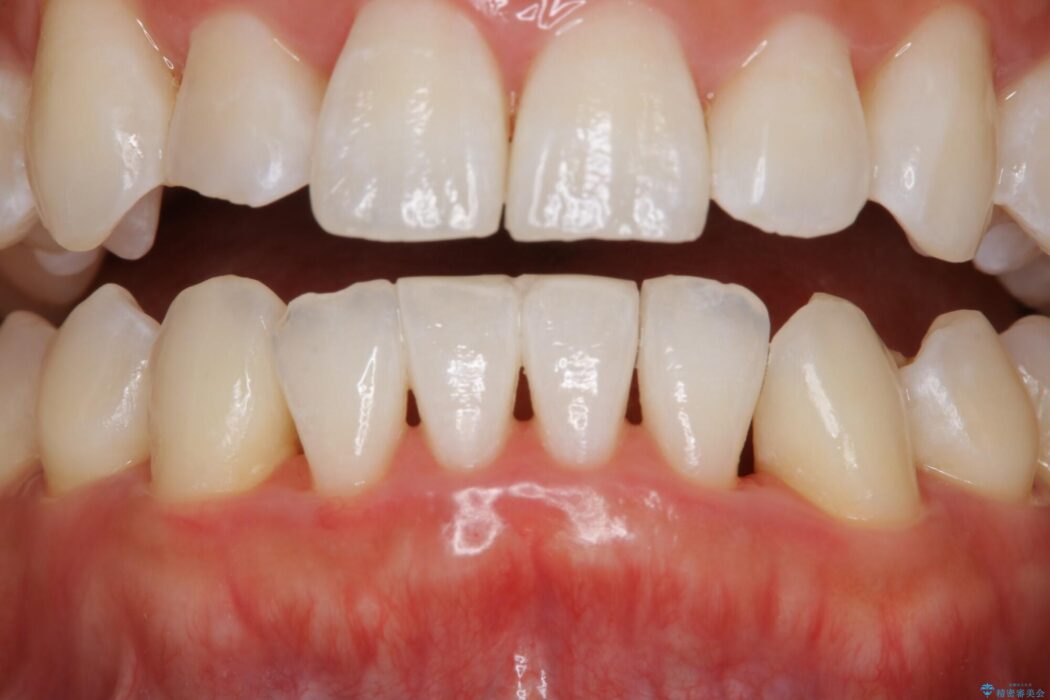

治療後について

審美的にも機能的にも回復し、治療後の仕上がりに満足していただけました。